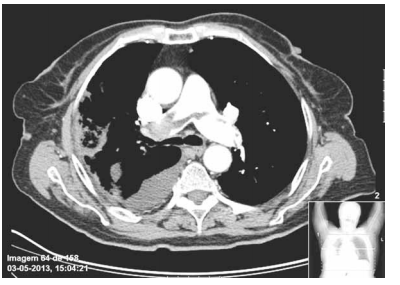

Mulher, 68 anos, sem antecedentes mórbidos, apresenta dor torácica ventilatório-dependente, de forte intensidade com piora à inspiração profunda e dispneia intensa. Recebeu alta há 15 dias após internação para cirurgia de correção de fratura de colo de fêmur. Exame físico: bom estado geral, taquipneica leve, afebril, PA = 120x70 mmHg, saturação periférica de oxigênio = 89% em ar ambiente, ausculta cardíaca normal e ausculta pulmonar com estertores crepitantes finos em bases. Realizados eletrocardiograma e tomografia computadorizada de tórax com contraste, ilustrados a seguir.